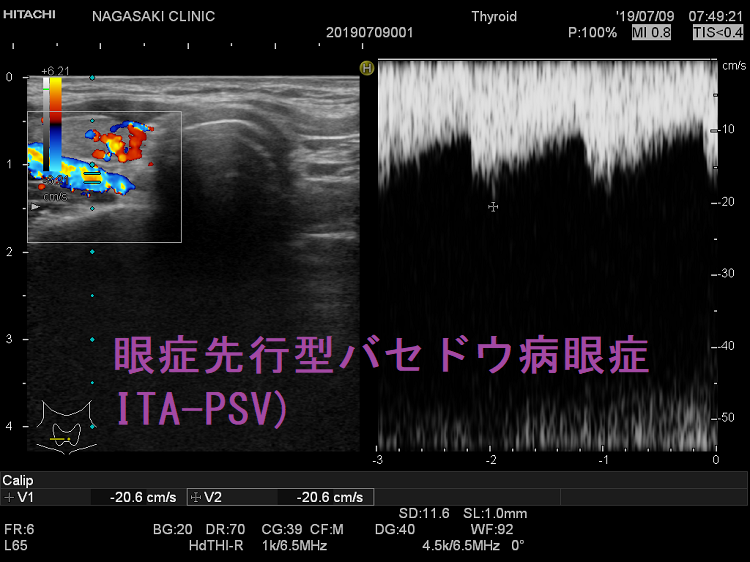

バセドウ病の約20%は、甲状腺ホルモンが高くなる前に眼症が先行します(眼症先行型バセドウ病眼症)。眼症先行型バセドウ病眼症は、甲状腺機能正常バセドウ病眼症より活動性が高いとされます。

甲状腺機能正常バセドウ病眼症は、眼症先行型バセドウ病眼症と異なります。伊藤病院の報告では

- 眼症発症後3年以上甲状腺機能正常なものを甲状腺機能正常バセドウ病眼症、3 年以内に甲状腺機能亢進症に移行したものを眼症先行型バセドウ病眼症と定義すると、手術治療(眼筋、眼瞼)まで行う症例が、

- 甲状腺機能正常バセドウ病眼症 5.7%(2/35例)

- 眼症先行型バセドウ病眼症 60%(3/5例)

と、眼症の活動性に明確な差があったそうです。(第57回 日本甲状腺学会 P1-016 眼症先行型バセドウ病(PGD)とEuthyroid Graves’ Disease(EGD)の眼所見についての検討)